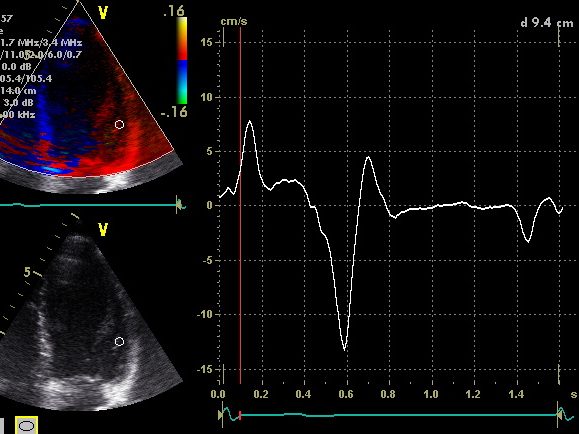

Mit Echokardiographie und Strain, TDI 3 D Verarbeitung kann ich fast alle Funktionen entdecken, analysieren und Ihnen helfen